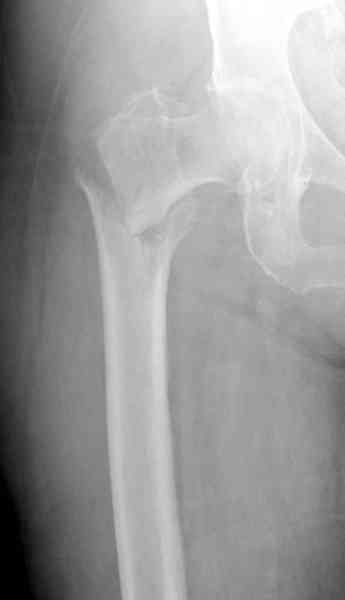

В общем, сделали. См. приложение.

Длина и из-за этого ось получились не совсем такие, как хотелось бы, все-таки срок после той операции уже 6 недель. Может быть, стоило провести дистракцию аппаратом неделю-другую. Заранее спасибо за комментарии и критику.